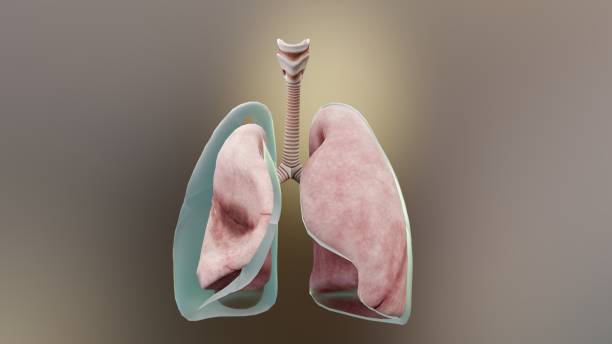

기흉(pneumothorax)은 폐와 흉부벽 사이에 공기가 쌓이는 상태를 말합니다. 이는 폐가 공기로 가득 차면서 폐가 축소되고 압축되어 발생합니다. 이러한 압축으로 인해 폐의 기능이 저하되며 호흡 곤란, 가슴 통증 등의 증상을 유발할 수 있습니다.

기흉은 크게 외상성 기흉과 비외상성 기흉으로 나눌 수 있습니다. 외상성 기흉은 외상이나 사고 등으로 인해 폐에 손상이 생기거나 뚫리면서 공기가 쌓이는 것이며, 비외상성 기흉은 폐의 질환으로 인해 공기가 쌓이는 것입니다. 비외상성 기흉은 폐기종증, 천식 등 다양한 원인에 의해 발생할 수 있습니다.